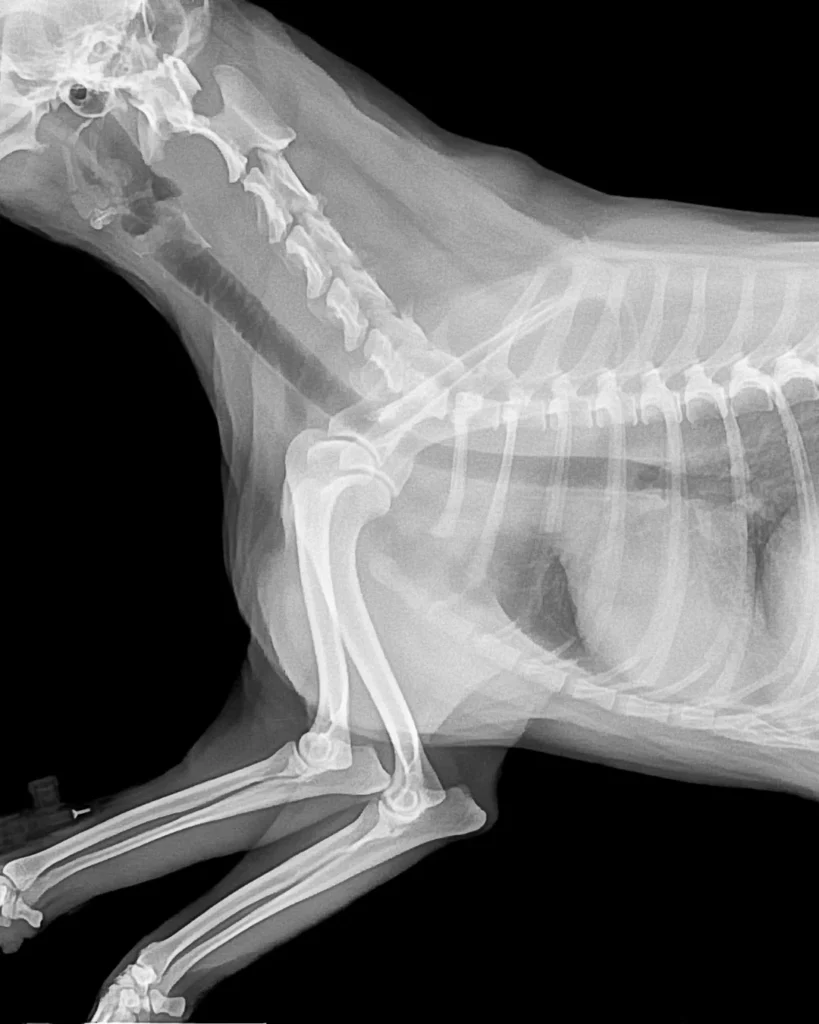

Digital Radiology (X-rays)

Our digital radiographs allow us to view internal structures such as bones, joints, lungs, and organs. This helps us diagnose:

- Fractures and joint issues.

- Internal injuries.

- Foreign objects.

Orthopedic imaging requires pets to remain still, and if necessary, we may recommend light sedation for comfort and precision.

Our dog X ray near me service is ideal for diagnosing joint injuries, fractures, hip dysplasia, or foreign object ingestion. We use pet-friendly positioning techniques to minimize stress and provide accurate results within minutes.

Cats often hide pain, which makes diagnosis tricky. Our gentle approach ensures minimal stress during cat X ray sessions. We can identify issues like respiratory problems, abdominal conditions, or bone injuries quickly and comfortably.

For comprehensive health checks, we offer full-body scans to detect any hidden abnormalities in the spine, lungs, abdomen, or limbs. This service is especially helpful for senior pets or those with chronic health conditions.

We use high-resolution digital radiography, which produces clearer images with minimal radiation exposure compared to traditional film X-rays.

- Accurate Diagnosis: Clear, digital X-ray images for fast detection of fractures, tumors, or internal blockages.